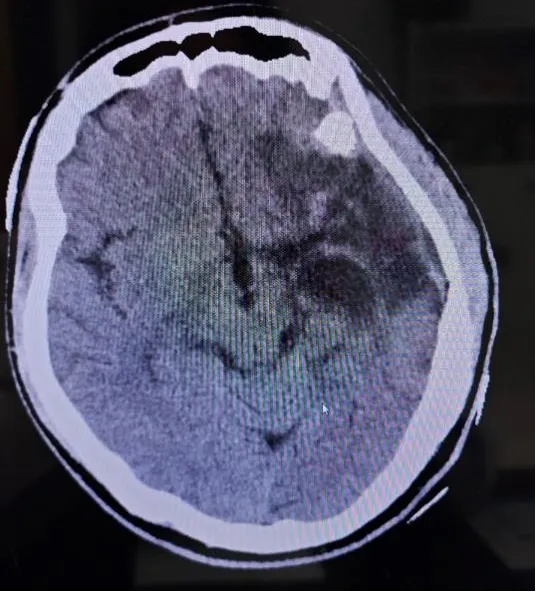

术中照片